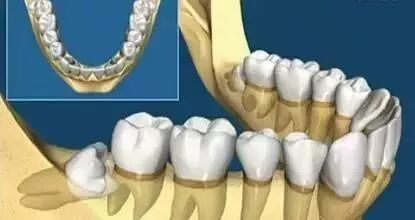

看看上图这些智齿的生长位置,真是千奇百怪。你觉得那颗最好拔?智齿但一旦生长位置出现了偏差,那就得科普另外一个词,阻生智齿

上面说过,小小的智齿也有很多分类,生长的姿势也不尽相同,这也就造成了想要拔除它的难易程度不一样。

又或者~他长成了下面任何一款: